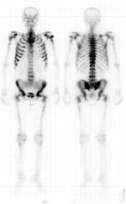

超级骨显像

肺性肥大性骨关节病